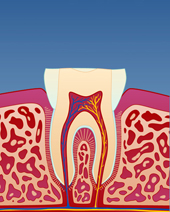

figur IV